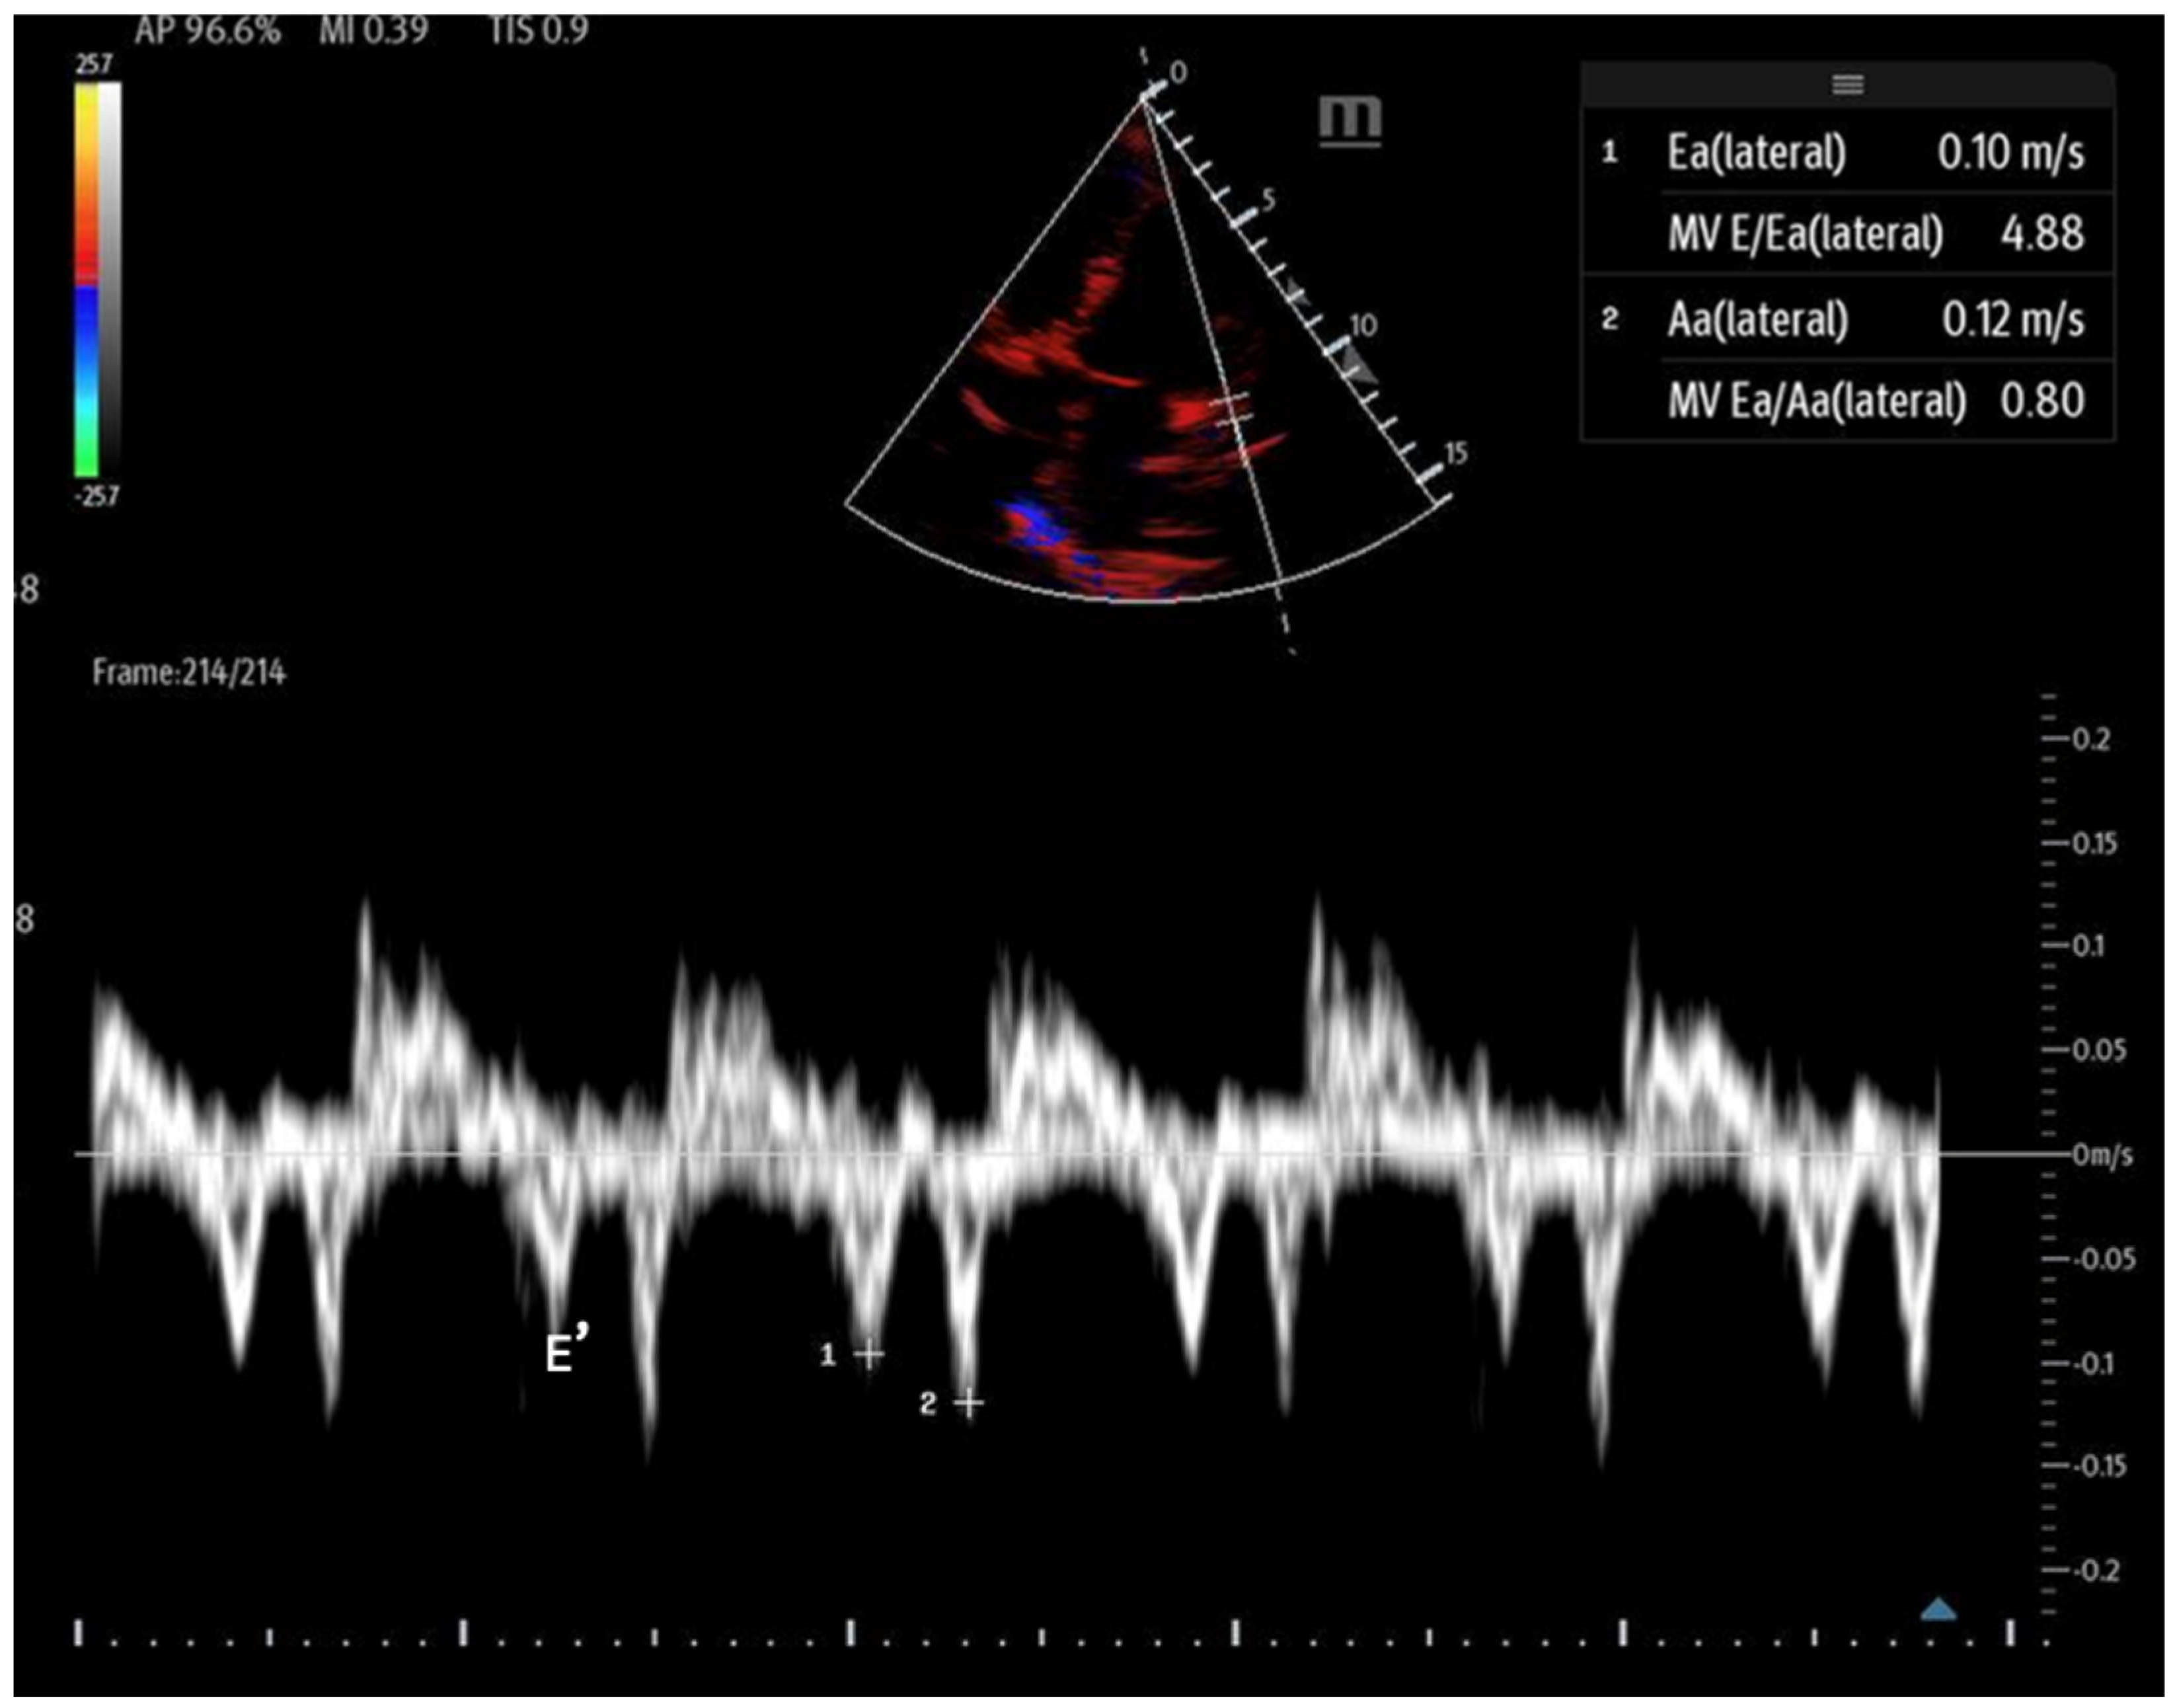

Figure 14. Mitral inflow with PW Doppler gate at mitral valve tip (E and A waves). - Tissue Doppler: Measures myocardial movement during diastole using tissue Doppler at the septal annulus. The E/e′ ratio is calculated from the recorded e′ wave (Figure 15).

Figure 15. Tissue Doppler at the lateral septal annulus to record the E′ wave (labeled).

When abnormal, these values can indicate diastolic dysfunction and its severity (Table 3). However, certain factors, such as mitral annular calcification, basal wall motion abnormalities, mitral stenosis, and significant mitral regurgitation, can affect mitral inflow velocities and invalidate measurements. Additionally, tachycardia may cause the fusion of the E and A waves, and atrial fibrillation can lead to variable RR intervals, further complicating accurate assessment [63]. It is important that while these assessments can be performed with bedside POCUS, accurately interpreting advanced diastolic parameters often exceeds the scope of non-cardiologist operators and may necessitate formal transthoracic echocardiography.